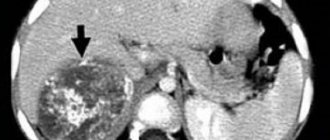

Incidentaloma of the adrenal glands (ICD 10 code: E2) - any formations in this area identified